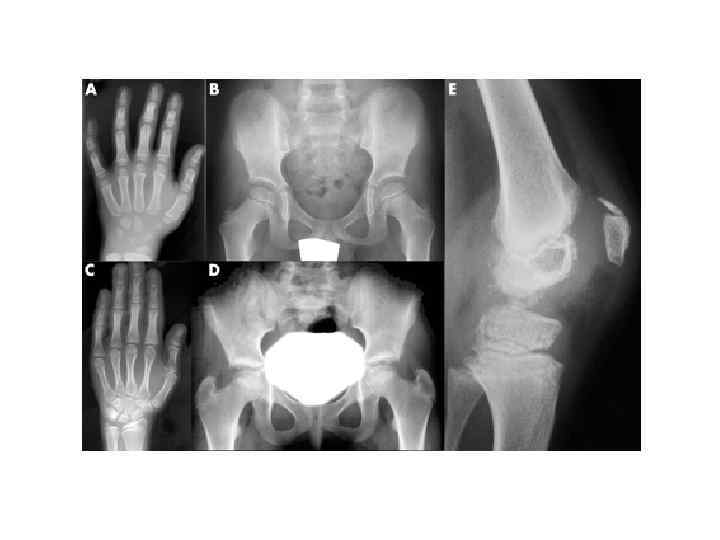

• А — қалыпты асықты жілік; Б — жетілмеген остеогенез; В — идиопатиялық остеопсатироз; Г — хондродистрофия; Д — остеохондродистрофия; Е — арахнодактилия; Ж — көптік шеміршектік экзостоздар; 3 — көптік сүйектің хондроматозы ; И — мәрмәр ауруы; К — мелореостоз; Л — остеопойкилия; М — туа біткен эпифизарлы нүктелік дисплазия; Н — туа біткен жүйелік диафизарлы гиперостоз.